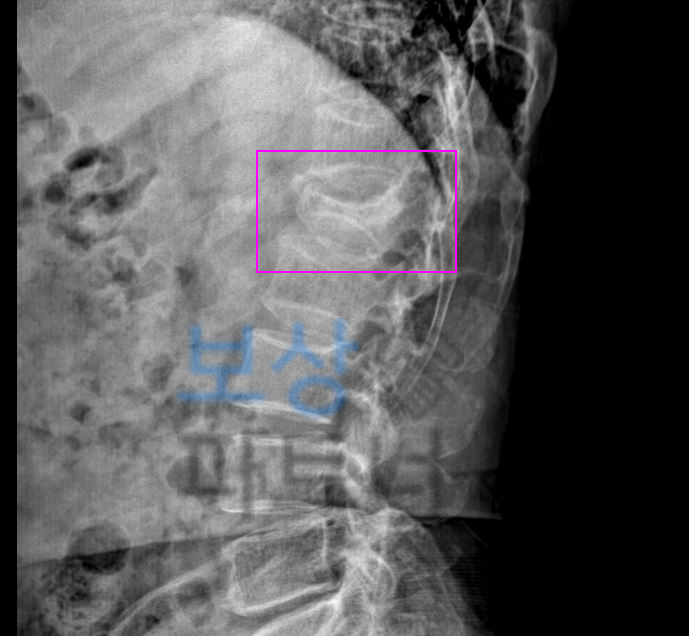

요추압박골절은 특히

척추 1번 부위의

발생 빈도가 높습니다.

요추1번은 흉추의 후만과

요추의 전만이 교차하는 부위로 미끄러지거나 허리 삐끗했을 때 검사하니 골절되거나 금갈 수 있습니다. 요추압박골절 1번척추 허리뼈골절 비수술 30% 4급 장해 보상

보상파트너로 문의해주셨던 서울시 거주 박@@님 또한 무거운 책을 드시다가 허리를 삐끗하셨다고 했는데요, 계속된 통증에 병원에 내원하여 Mri 등 정밀 검사를 받으셨고 진단 결과

L1 척추 요추압박골절

S32020 진단받으셨습니다. 박@@님은 수상일로부터 약 8주간 TLSO 허리보조기 착용하며 비수술 보존치료 진행하셨는데요, 장해보험금 청구를 위해서는

영상CD 및 영상판독지를 보면 Acute compression fracture in L1 **급성 요추압박골절 **확인됩니다. 보상파트너는 보험사도 인정할 공신력있는 상급병원 전문의로부터 후유장해 평가 받았고